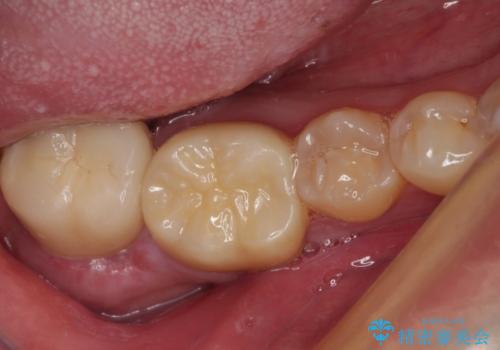

検査で見つかった虫歯 セラミッククラウンでの治療

担当医 岡田康成